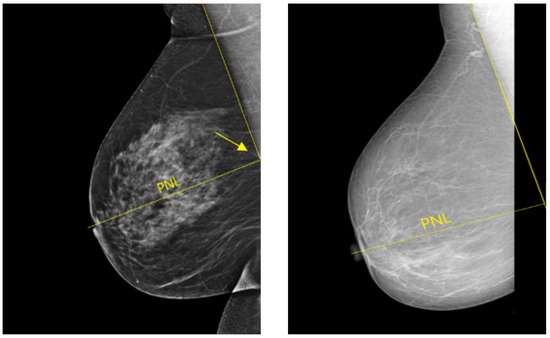

In a well-positioned MLO view, the lower edge of the pectoralis muscle should be at the level of the posterior-nipple line (PNL) or below (see Figure 20). The PNL refers to a line drawn from the nipple posteriorly and perpendicularly towards the pectoralis muscle line [40]. This demonstrates that the mammogram includes adequate coverage of the posterior breast tissue. There is a risk of breast tissue exclusion, which is necessary for effective breast cancer detection, if the PNL does not intersect the pectoralis muscle line within the image area (Figure 20).

Figure 20. Example of adequately and inadequately positioned MLO views. (Left): a well-positioned MLO view in which the pectoralis muscle line and the posterior nipple line (PNL) intersect within the image area (cf. yellow arrow). (Right): an inadequately positioned MLO view where the pectoralis muscle line and the PNL do not cross within the image area.